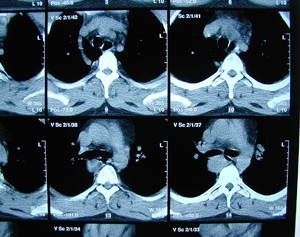

Εικόνα 2 α-γ

Αξονική τομογραφία του θώρακος σε διαφορετικά επίπεδα. Διακρίνεται η παρουσία όγκου στο οπίσθιο μεσοθωράκιο που πιθανά να αποτελεί όγκο του οισοφάγου.